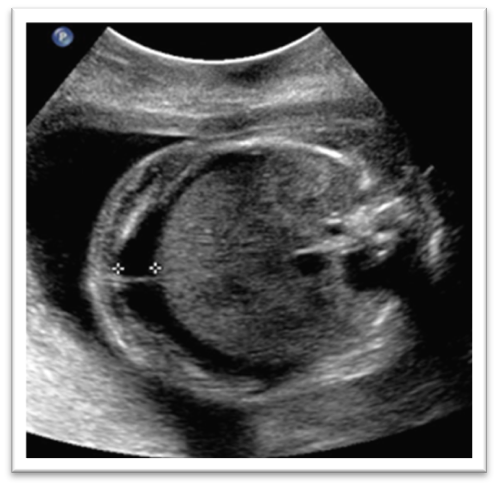

What is this image showing?

True ascites